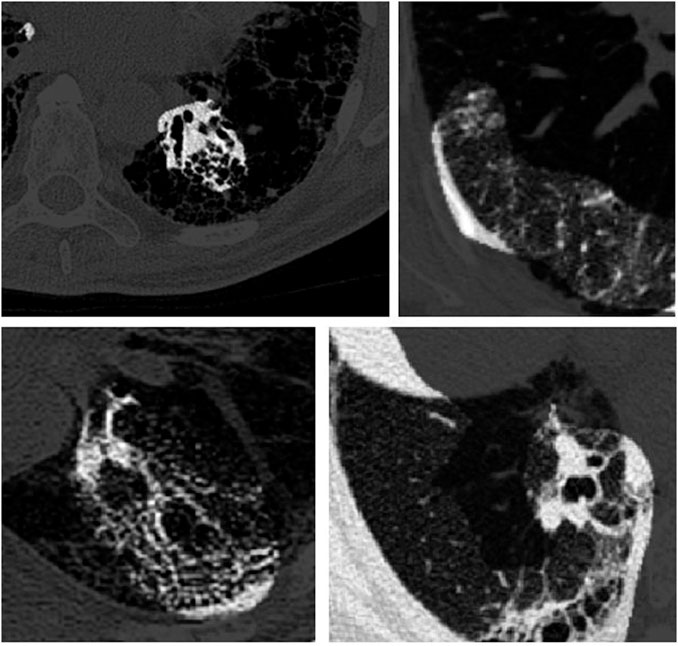

The data processing pipeline used in this study is as follows. A number of pre-processing steps were conducted to improve the consistency and quality of the CT images from the patient scans. More specifically, all CT imaging data was translated to Hounsfield units (HU), and windowing was performed with a window level of -650 HU and a window width of 1700 HU to better focus on clinically relevant lung features. Furthermore, synthetic padding and circular artifacts found in the CT imaging data for several patient cases within the patient cohort are mitigated to reduce the likelihood of erroneous visual features from being learned as predictive indicators. Finally, calibration value errors found in the data for several patient cases within the patient cohort are accounted for to further mitigate the likelihood of erroneous characteristics from being learned as predictive indicators. Example CT slices from the patient cohort are shown in Figure 1. It can be observed that the visual appearance of pulmonary fibrosis in different patient CT scans can be quite varied, and thus can be quite challenging to utilize for lung function decline prediction. The variable visual appearance in CT scans further motivate the exploration of deep learning strategies for tackling such a complex prediction task to facilitate for computer-assisted clinical decision support.

FIGURE 1

FIGURE 1. Example CT slices from the patient cohort from the OSIC Pulmonary Fibrosis Progression Challenge (OSIC, 2020).